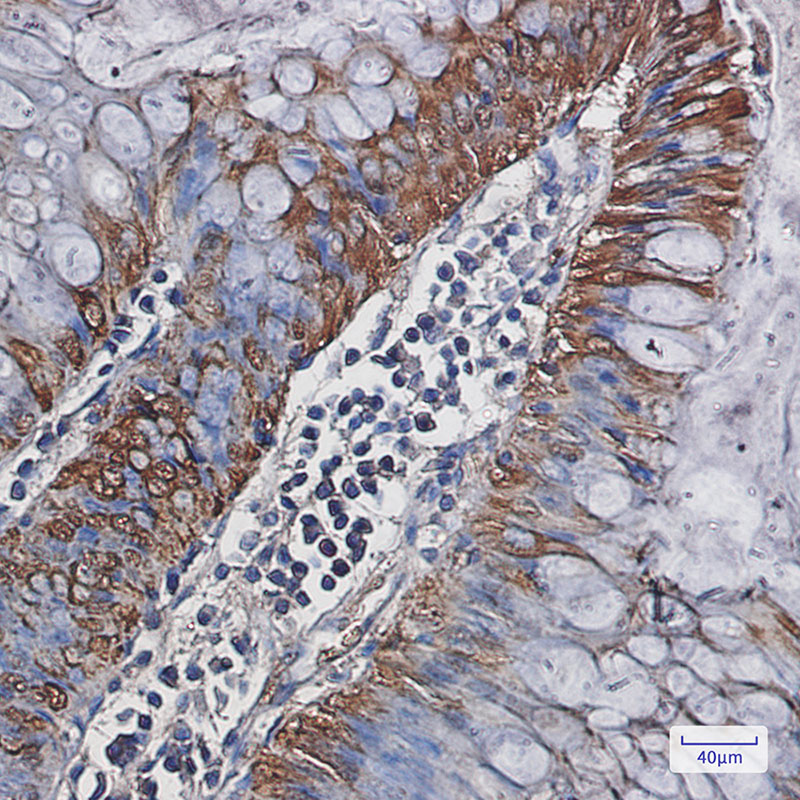

IHC 1/50-1/100 Human,Mouse,Rat

Antibodies targeting CA1 are valuable tools in biomedical research and diagnostics. They are widely used to study CA1's expression patterns, cellular localization, and functional roles in both normal and pathological conditions. For instance, CA1 antibodies have been employed in Western blotting, immunohistochemistry, and ELISA to investigate its dysregulation in cancers (e.g., colorectal, pancreatic), where altered CA1 levels may correlate with tumor progression or metabolic reprogramming. Additionally, CA1 autoantibodies have been detected in autoimmune disorders, such as rheumatoid arthritis and ulcerative colitis, suggesting a potential link to disease mechanisms.